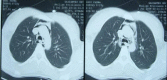

Figure 2

Chest CT revealed marked air accumulation around the aorta, trachea, and pericardium. Deep cervical emphysema was also observed.